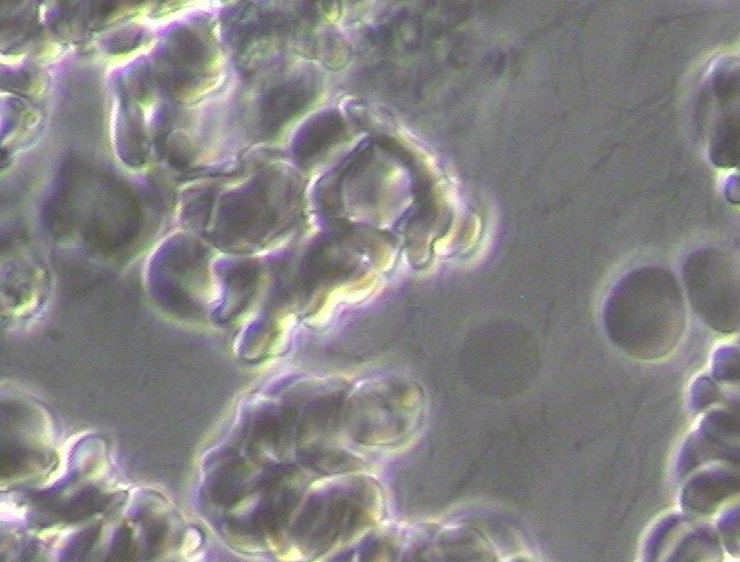

Pathological blood coagulation or disseminated intravascular blood coagulation (DIC) inside the pulmonary vein will prevent the free passage of red blood cells into the alveoli of the lungs via the pulmonary capillaries. {See Phase Contrast Micrograph 3 and 4) Erythrocytes or red blood cells must go into the pulmonary capillaries single file. If they cannot pass into the pulmonary capillaries of the lung to the alveoli this will cause oxygen deprivation that leads to red blood cell hypoxia (carbon dioxide poisoning) degeneration, genetic mutation, sepsis and sudden death.[6][7][8]

Live and Dried Blood smears are both non-invasive blood tests that were used in viewing anatomically the conditions of the red and white blood cells in Disseminated Intravascular Coagulation (DIC), Thrombosis, Rouleau, the ‘Corona Effect’ and Acanthocytosis. (See Phase Contrast Micrograph 7)[12]